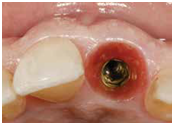

98/01/08經過三個半月做右下第一小臼齒的二階暴露,發覺鄰牙的植體高度竟已掉下來

980305幫患者補角化牙齦並翻開清除發炎組織,期待能阻止繼續骨破壞